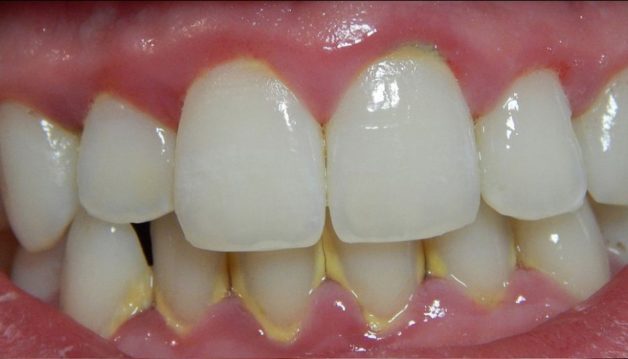

- Bước 3: Sau khi hoàn tất công đoạn lấy cao răng, bác sĩ sẽ bắt đầu đánh bóng bề mặt răng bằng các dụng cụ chuyên dụng nhằm giúp răng của bạn sáng bóng và hạn chế sự tích tụ của các mảng bám sau này.

Nha khoa Hanseoul hiện nay được biết đến là một trong những địa chỉ nha khoa uy tín hàng đầu Việt Nam với các dịch vụ đều được áp dụng công nghệ hiện đại và có mức giá hợp lý. Khách hàng khi đến lấy cao răng tại Hanseoul sẽ được thực hiện bằng máy Piezotome cam kết không đau nhức, không chảy máu và khắc phục được mọi nhược điểm của các phương pháp cũ. Với công nghệ này, các mảng bám cao răng sẽ được loại bỏ sạch sẽ và nhanh chóng, hạn chế tối đa tình trạng vụn thức ăn bám vào nướu răng và hiệu quả lâu dài.